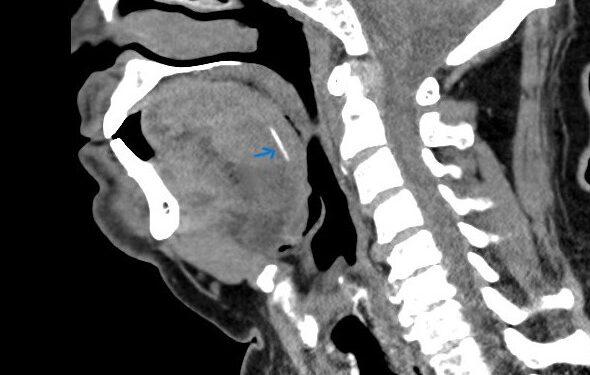

תושב סח’נין בן 65, אשר חש כאבים עזים בפיו לאחר אכילת דג, פונה למרכז הרפואי זיו בעקבות זיהום ונפיחות בלשונו. בעקבות ערנותו של ד”ר ג’מאל גנטוס, מתמחה א.א.ג, בוצעה בדיקת CT שאבחנה עצם דג באורך 2 ס”מ הנעוצה בעומק הלשון של המטופל ועלולה הייתה לסכן את דרכי הנשימה. בניתוח יוצא דופן, תחת הדמיית אולטרסאונד בזמן אמת, הצליח צוות מומחי המרכז הרפואי זיו, לשלוף את העצם בהצלחה.